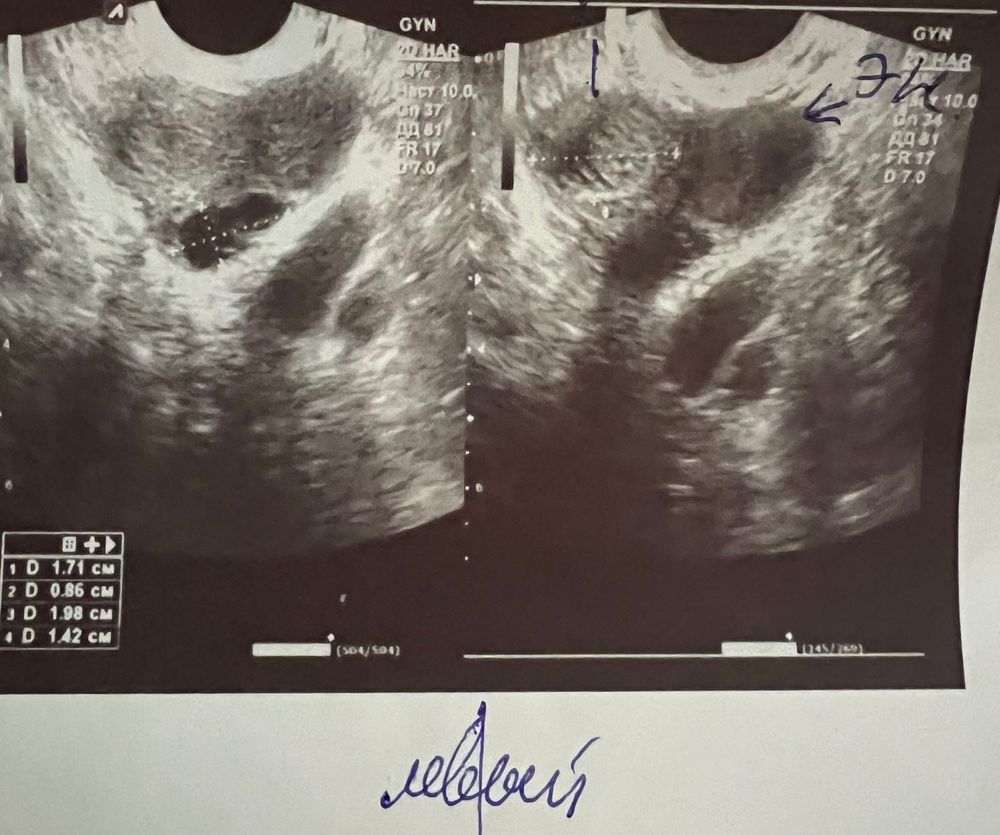

УЗИ киста с перегородкой

Киста яичника. Главное что без кровотока. Надо к гинекологу с ней. И наблюдать. Может дать регресс

Гипоплазия эндометрия,фолликулярная киста Месячные